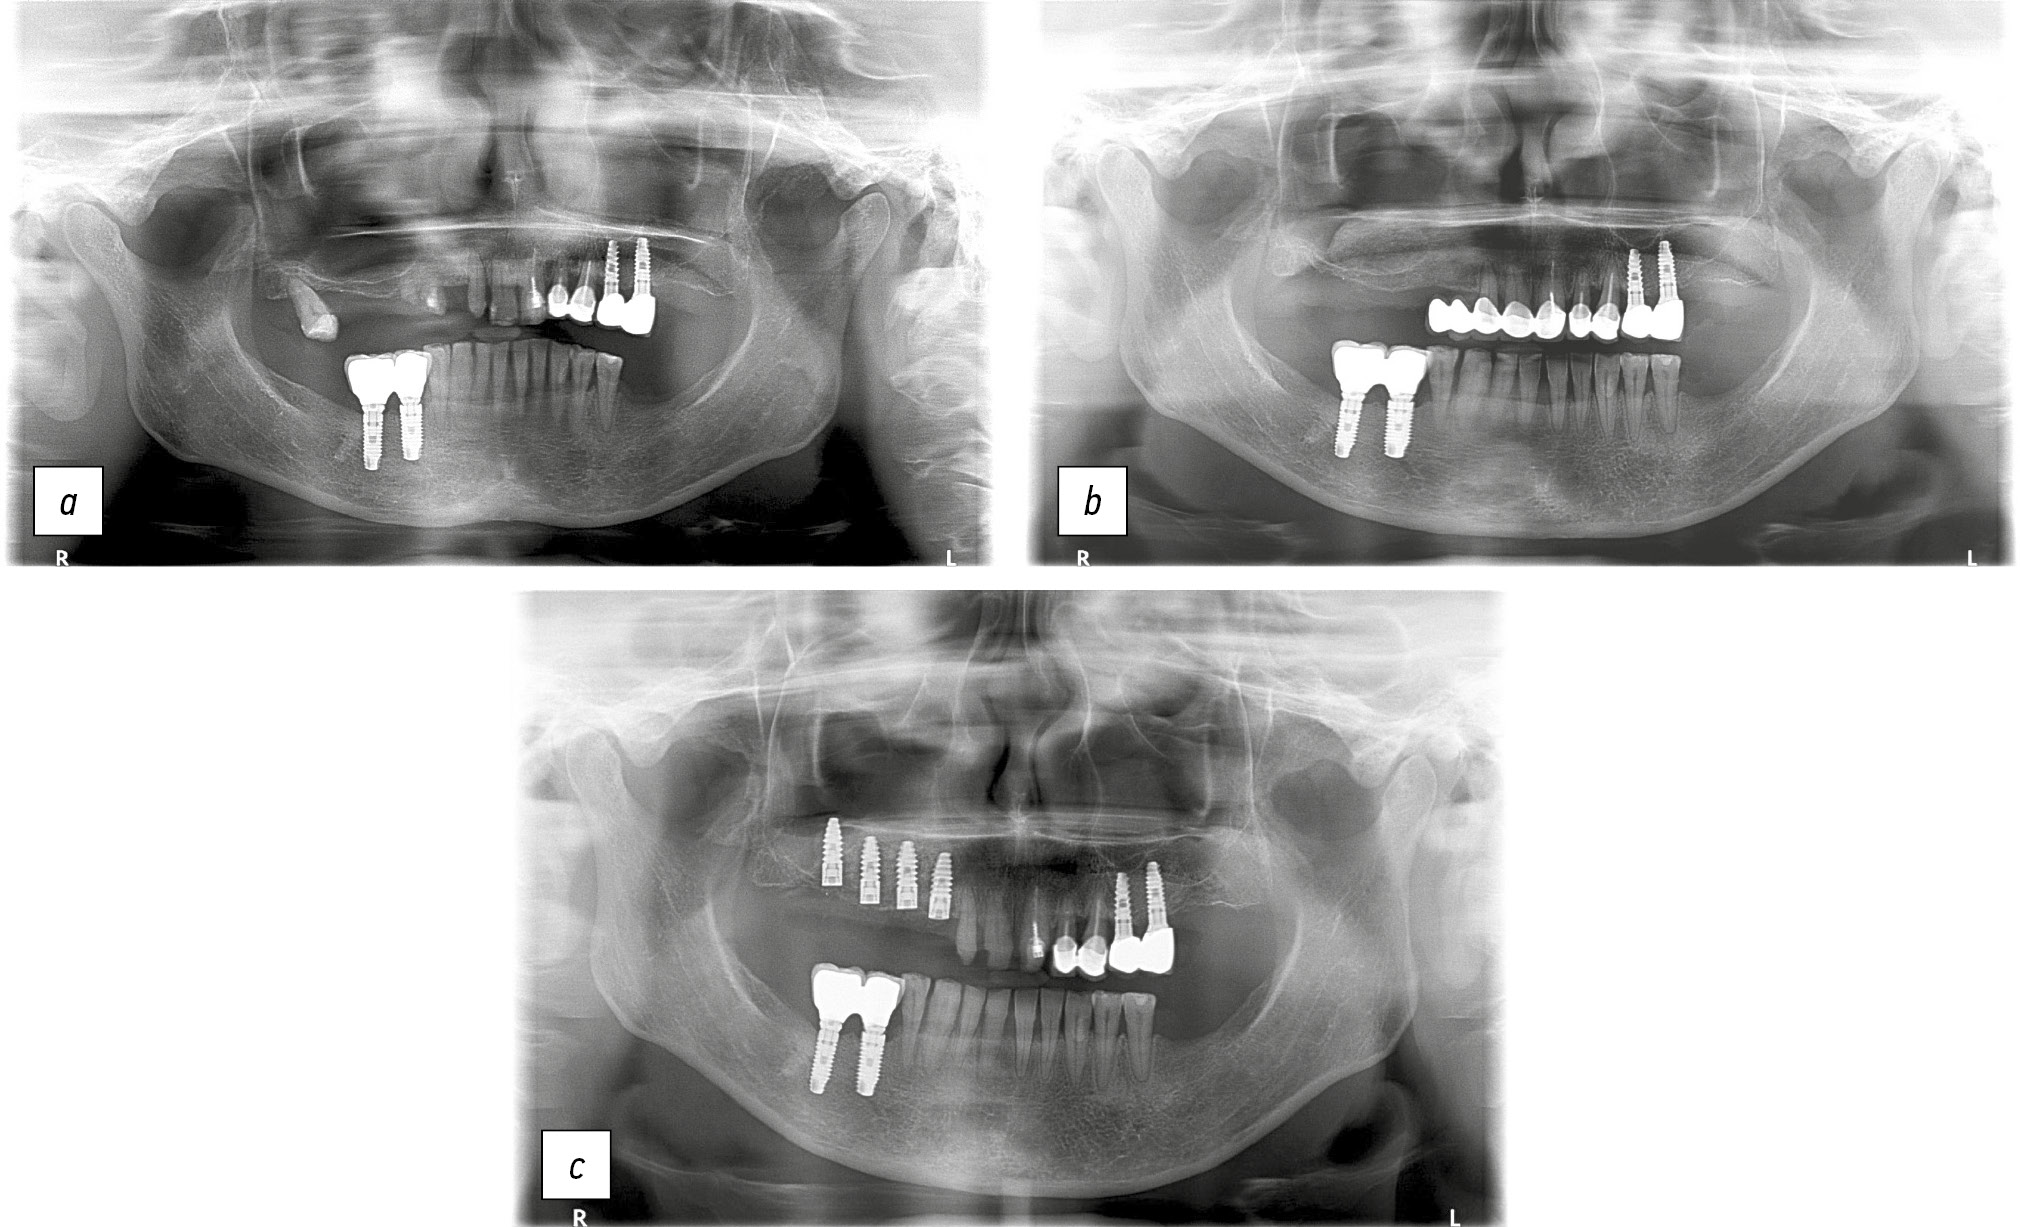

В качестве клинических примеров приводим ортопантомограммы пациента Ч. и пациентки Б. до и после аугментации лиофилизированной губчатой костной тканью (рис. 5, 6).

Рис. 6. Ортопантомограммы пациентки Б.: a — исходная клиническая ситуация; b — проведена аугментация с использованием лиофилизированной губчатой костной ткани; c — установлены дентальные имплантаты, этап остеоинтеграции.